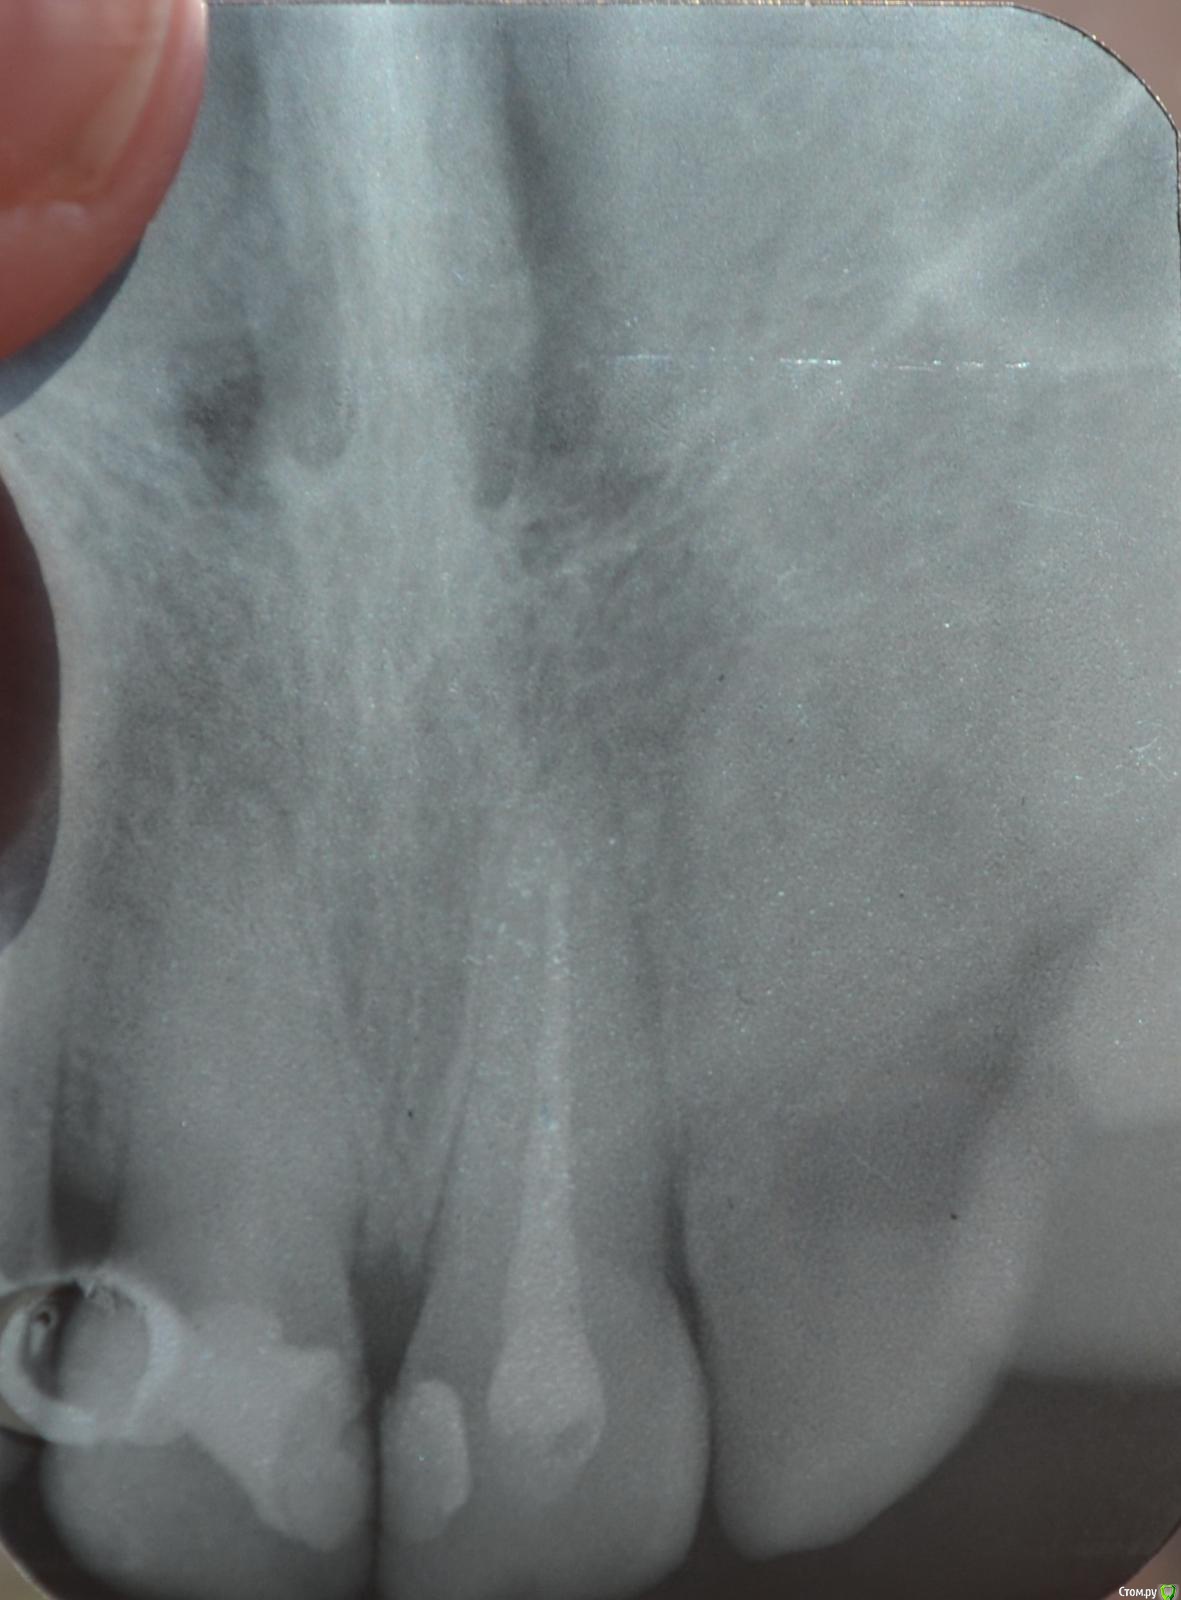

Llllll Опубликовано 11 июля, 2015 Автор Поделиться Опубликовано 11 июля, 2015 1 справа верхний, до того как открыли недавно каналы. Ссылка на комментарий

Llllll Опубликовано 12 июля, 2015 Автор Поделиться Опубликовано 12 июля, 2015 Лучше бы прицельный снимок проблемного зуба(на ОПТГ ничего не видно).Это 2 снимка этого зуба, несколько раз сфотографировала, чтоб лучше было видно. Ссылка на комментарий

Llllll Опубликовано 12 июля, 2015 Автор Поделиться Опубликовано 12 июля, 2015 И есть ли воспаление корня на снимке? (правого или левого). Вообще врач думал во вторник удалять передний зуб, который болит. К другому врачу не могу пойти, так как город маленький, и врачей всего несколько. Это уже третий врач у которого была, и никто не знает что с зубом делать, и вообще от него ли это( Ссылка на комментарий

Llllll Опубликовано 16 июля, 2015 Автор Поделиться Опубликовано 16 июля, 2015 Сегодня делали рентген еще раз, и увидели на 1 зубе справа (тот, который болит) на самой верхушке корня кусочек инструмента. Рентгена нету, так как его на компьютере только смотрели. Сказали что достать его нельзя. Что делать? Ссылка на комментарий

Llllll Опубликовано 27 июля, 2015 Автор Поделиться Опубликовано 27 июля, 2015 Вот еще делали рентген с иголкой в зубе. Ссылка на комментарий